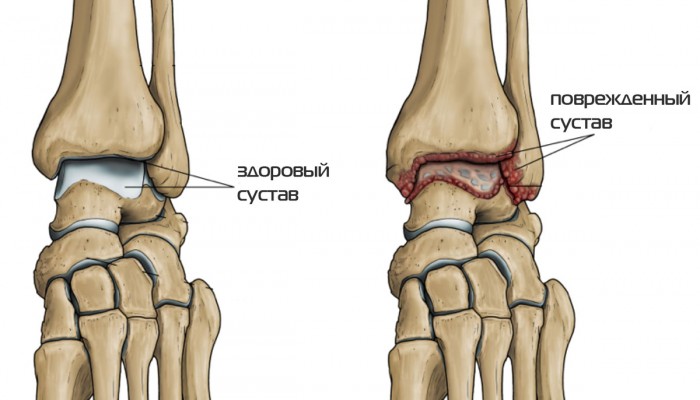

Деформирующий остеоартроз голеностопного сустава (ДОА) – тяжёлое заболевание, приводящее к инвалидности, если вовремя не начать лечение. Начальная стадия всегда протекает бессимптомно. ДОА характеризуется разрушением хряща (дегенеративные изменения), воспалением суставной капсулы, разрастанием остеофитов, ослаблением связочного аппарата.

При дальнейшем развитии заболевания (III степень) сустав всё больше деформируется, суставная щель уменьшается. Наблюдается значительное ограничение подвижности. Попытка повернуть стопу в нужном направлении вызывает боль. Наблюдается явно выраженный субхондральный остеосклероз, разрастание костной ткани (остеофиты) сильное.

IV степень – повод обратиться в медкомиссию за получением инвалидности. Суставная щель полностью отсутствует. Костные образования (остеофиты) прочно фиксируют сустав в вынужденном положении. Деформация может дополняться подвывихом. Эпифизы составляющих сустав костей сильно уплотнены.